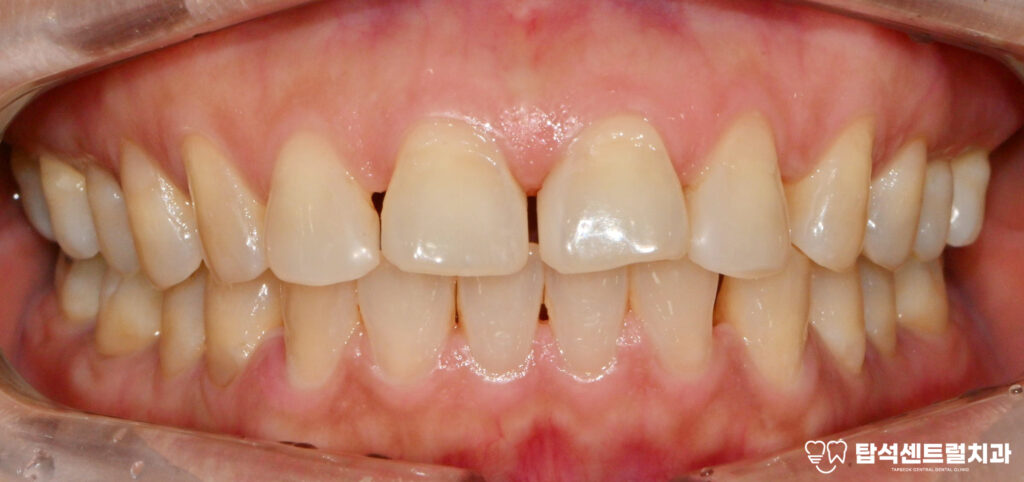

치주염으로 인한 치아 통증을

어떤 방법으로 해결할 수 있는지

고산동 치과 에서 소개해드리겠습니다.

왼쪽 위 아래 어금니에서

통증이 느껴진다면 잇몸 염증을

의심해볼 필요가 있습니다.

특히 음식을 먹을 때 불편함이

지속되거나 이가 흔들리는

느낌이 든다면, 치주 질환이

꽤 오랫동안 진행되어왔을

가능성이 높습니다.

특히 심한 치아 통증을

동반하는 경우 치주염 증상이

유력해집니다.